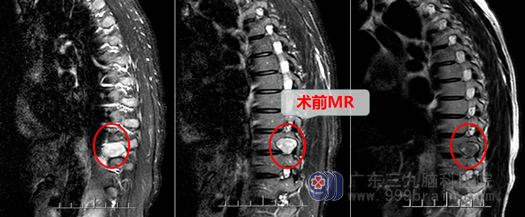

33岁的吴女士原本家庭幸福,生活美满,却因为一场突如其来的疾病打破了她原本幸福美满的生活。一个月前吴女士突然出现双下肢感觉减退,行走不稳,无头疼、头晕、恶心呕吐等症状,家属立即带她到当地医院做了脊椎磁共振检查,显示:胸10椎体水平椎管内及胸10/11椎间孔区占位,考虑神经源性肿瘤。考虑到手术的风险和安全,她和家人选择到广东三九脑科医院神经外十科住院。

神经外科主任欧阳辉教授看到病人后详细的评估的吴女士的情况:肿瘤已压迫到神经,下肢功能、感觉已逐渐减退,再进一步发展就会出现脊髓横贯性损害:下肢就会瘫痪,大小便不能控制。所以手术治疗刻不容缓。为了将手术损伤降到最低,尽最大的可能保护功能,医生团队决定采用微创手术:即在一个微小的套筒内,在显微镜放大下全部切除肿瘤。由于肿瘤向椎管内已压迫脊髓,经过椎间孔已凸向胸腔,故这种手术也存在损伤脊髓、神经,甚至撕破胸膜,导致气胸的危险。主管医生邓心情与家属进行了耐心、细致的解释、沟通后,家属决定同意医生方案进行手术。在完善相关检查后,吴女士被安排在全麻下行“T10-11段椎管椎间孔内外肿瘤微创切除术”。手术进行得非常成功,肿瘤被完全切除,而脊髓、神经、胸膜都得到了完好的保护,没有被损伤。术后第二天吴女士的腿都可以抬起来了,明显比术前好很多,感觉也恢复了,术后第五天,在医生和护士的帮助下已可以下床走路了,也没有出现任何的大小便功能障碍。